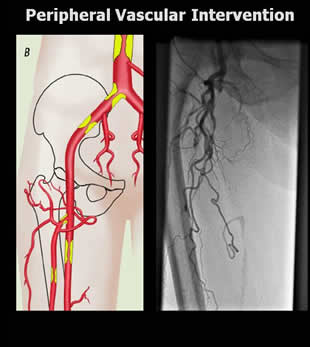

Peripheral Interventions

When patients suffer from hardening of the arteries, or atherosclerosis, their arteries are partially blocked by a substance called plaque. When these blockages occur in the legs or arms, they are called peripheral artery disease. Peripheral vascular interventions remove the plaque and restore the flow of blood through the artery. These interventions are medical specialties that treat peripheral artery diseases without surgically opening the leg or arm. Instead, the doctor uses small tools and at least one catheter. A catheter is a thin tube that is inserted into a blood vessel through a small cut, usually in the leg or arm, and threaded to the site of disease. Once in place, it acts as a tunnel, enabling the doctor to efficiently guide the tools to where they are needed.

The muscles and other tissues of the arms and legs need oxygen and nutrients to work. If the arteries that feed the arm or leg are blocked by plaque (a mixture of cholesterol, fat, calcium and other substances), the leg will not work well and may experience pain or numbness. In extreme circumstances, they may require amputation. By using a catheter, doctors avoid making large surgical cuts when they remove the blockage. As a result, procedures that rely on a catheter generally decrease pain, pose less risk of infection, avoid large scars and shorten recovery times. In some cases, the patient may go home the same day.